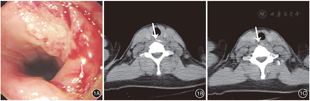

患者女,45岁,因误吞鱼刺致咽痛及异物感12 d就诊。患者入院前6 d曾在外院行胃镜检查提示食管入口处透明鱼刺样异物,因局部黏膜出血未行异物取出术,予保守治疗,咽部疼痛及异物感无缓解,病程中无呕血、发热等症状。在我院门诊行胃镜检查见食管入口一大小约1.0 cm×1.0 cm凹陷灶,基底白苔,周围黏膜充血水肿,食管腔内未见明显异物残留(图1A)。予胸部CT检查,提示食管胸廓入口处(约颈7水平)见条状高密度影,长径约2.3 cm,水平略向左下走行(图1B),周围软组织肿胀、脂肪间隙模糊,见多处气体密度影(图1C),初步诊断:颈段食管异物并穿孔。血常规、C反应蛋白无明显异常。经与患者充分沟通病情及治疗方案,患者同意行内镜下治疗。入院后第2天复查无痛胃镜,食管腔内仍未发现异物,超声胃镜检查亦未探及食管壁内外异常回声影。胃镜下予1枚和谐夹(ROCC-D-26-195,南微医学,中国)夹闭溃疡灶肛侧,行食管薄层CT扫描(每层间隔2 mm)并行三维重建,明确异物与止血夹的相对位置。食管三维CT重建可见鱼刺位于止血夹左后方(图2)。定位后行内镜下病灶处黏膜及肌层切开术。手术过程如下:根据和谐夹与CT定位后相对关系(图3A),于和谐夹左后方,应用Dual刀逐层切开黏膜及环形肌(图3B);切开后见嵌入食管壁外的鱼刺;使用透明帽进一步钝性分离切开的食管黏膜及肌层,暴露鱼刺(图3C、图3D);应用异物钳夹取鱼刺,配合透明帽将鱼刺完整取出(图3E、图3F)。术中全程使用二氧化碳气泵,避免术中穿孔导致或加重皮下气肿。术后予禁食3 d,使用头孢拉定+奥硝唑联合抗感染、抑酸及补液等治疗。术后第4天,患者异物感症状消失,咽痛等不适缓解出院。出院后电话随访无咽痛、发热等不适,2周后复查胃镜提示病灶处黏膜愈合。